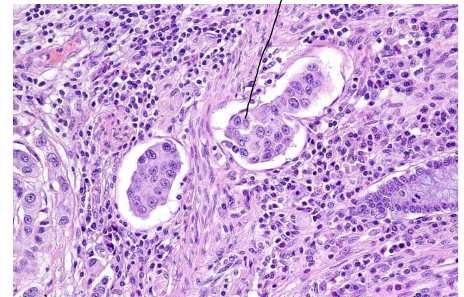

What is this?

• Lymphovascular invasion

• cancer cells in small vessels suggesting metastasis